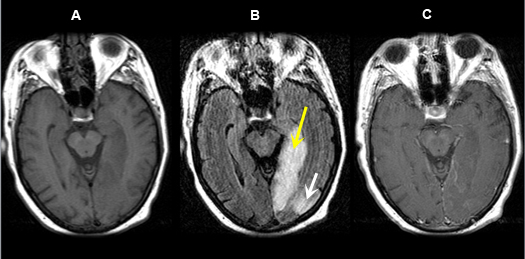

Figure 5 A-C: MR Images

|

Posterior cerebral artery territory Acute Stroke

Case 5:

Imaging findings: Figure 5 A-C

- Pre-contrast axial T1 wtd. MRI

- Axial flair image

- Post-contrast axial T1 wtd. MRI

Acute infarction is seen involving the left occipital lobe (yellow arrow) and adjacent left temporal lobe (white arrow). The left posterior cerebral artery territory infarction is better seen on flair sequence (Fig. B) than on T1 wtd. pulse sequence (Figs. A, C).

|

Figure 5 D-E: MR Images

|

Imaging findings: Figure 5 D-E (DW images)

Acute infarction involving the left occipital lobe (yellow arrow in Fig. A), adjacent left temporal lobe (white arrow in Fig. D) and infarction within the left thalamus (red arrow in Fig. E) is best appreciated on diffusion wtd. pulse sequences. |